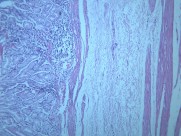

慢性萎缩性胃炎大全(12)张

本病以胃粘膜萎缩变薄,粘膜腺体减少或消失,并伴有肠上皮化生,固有膜内多量淋巴细胞、浆细胞浸润为特点。本性胃炎的病因比较复杂,部分可能与吸烟酗酒和用药不量有关,部分由慢性浅表性胃炎迁移发展而来,还有部分属兔自身免疫疾病。